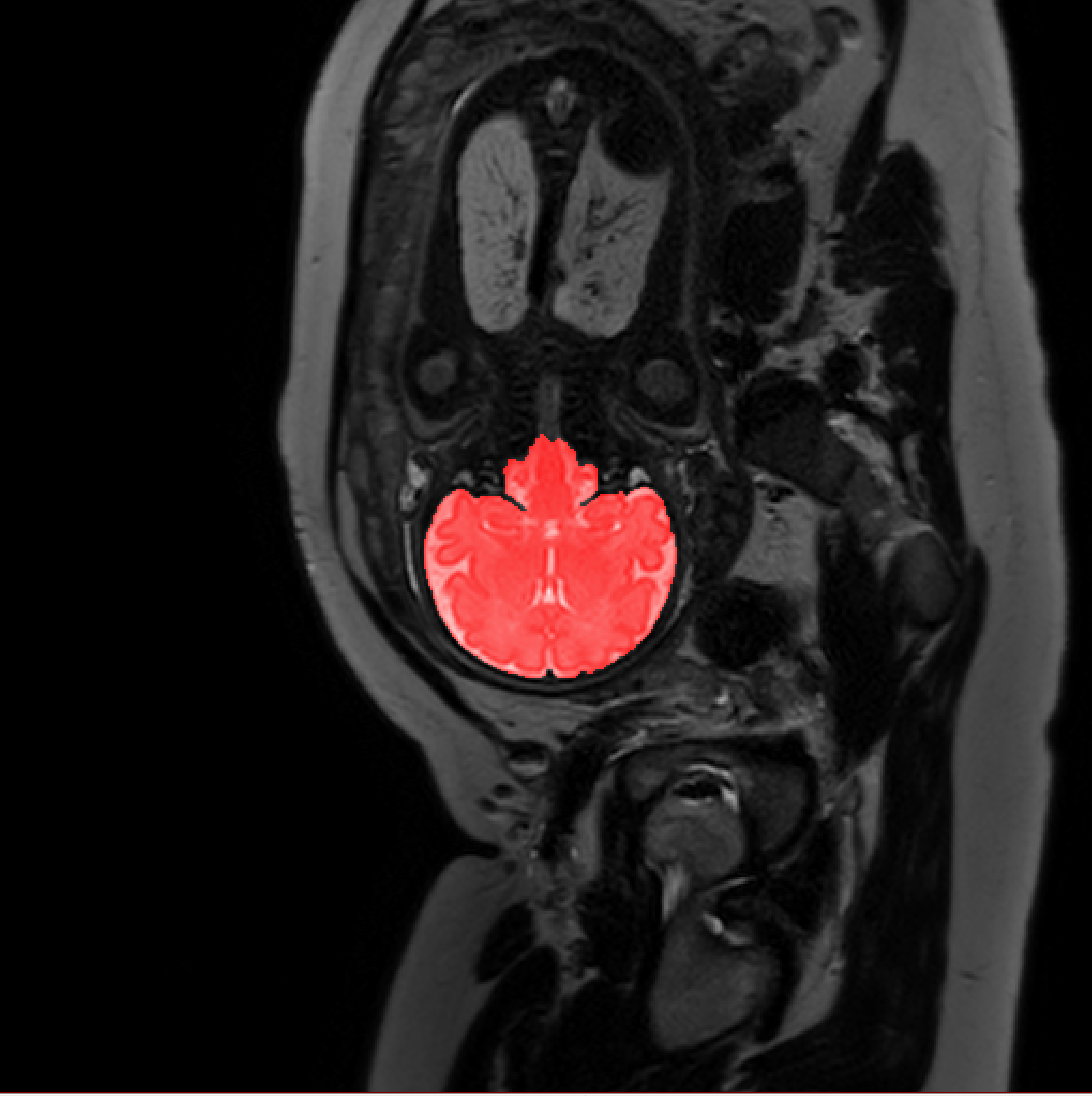

Table 1 lists average of quantitative evaluation results of these experiments and Figure 2 shows results obtained from each image. Figure 3 shows examples of the obtained segmentations.

Figure 3: Example of ICV segmentations in images acquired in axial (left), coronal (middle) and sagittal (right) planes. Top row: A slice from T2-weigted image; Second row: Automatic segmentations obtained using 7 training images from the representative imaging planes; Third row: Automatic segmentations obtained using all 21 training images from all 3 image orientations; Bottom row: Manual segmentation.